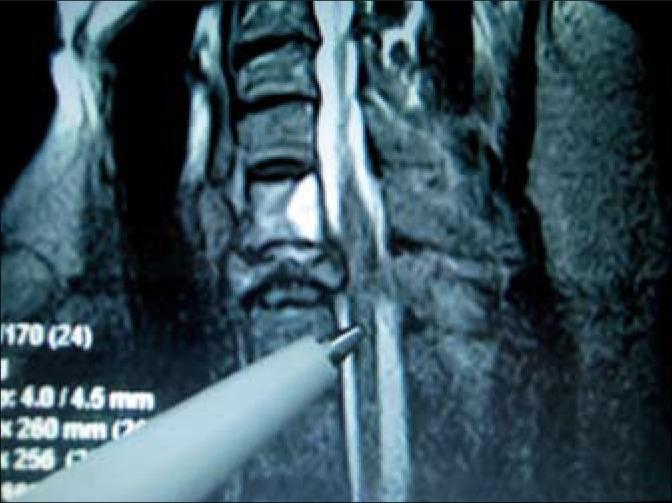

Prostate cancer (PCa) is a major health problem and one of the main causes of cancer mortality in men [1]. In patients with PCa, bone metastases manifest in 100% of patients when the PSA level exceeds 100 ng/ml causing pains and posing a risk for pathological fractures [2]. We report a case of a 70-year-old male with PCa and pathological fractures of the vertebrae, in whom we observed long-term regression and an 8-year-survival while undergoing continuous therapy. As far as we know, this is the first reported case in literature with such an unexpected outcome.